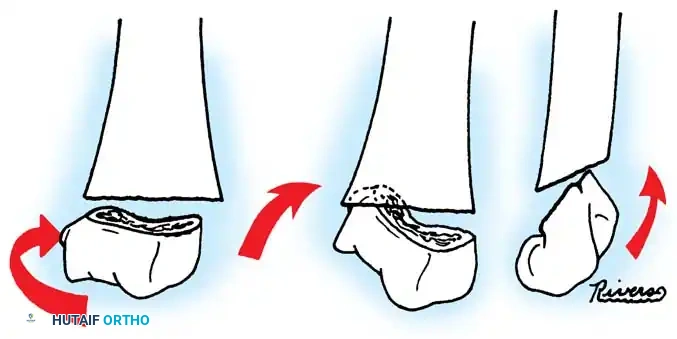

The Metaizeau Technique (Elastic Stable Intramedullary Nailing)

Gonzalez-Herranz et al. and Metaizeau revolutionized the treatment of displaced radial neck fractures (O’Brien types II and III) using retrograde intramedullary pinning. This technique boasts excellent results in over 94% of cases.

- Entry Point: A small incision is made over the distal lateral radial metaphysis, taking care to protect the superficial radial nerve.

- Pin Preparation: A steel Kirschner wire or titanium elastic nail (TEN) is sharply bent at the distal 1.5 cm.

- Insertion: The wire is advanced retrograde through the medullary canal until the bent tip engages the displaced proximal epiphysis.

- Reduction: The pin is rotated 180 degrees around its long axis. The bent tip acts as a cam, elevating the radial head and shifting it medially into anatomical position beneath the lateral condyle.

Fig. 33-44 A-D, Reduction of radial head by leverage method and retrograde intramedullary pinning with Kirschner wire.